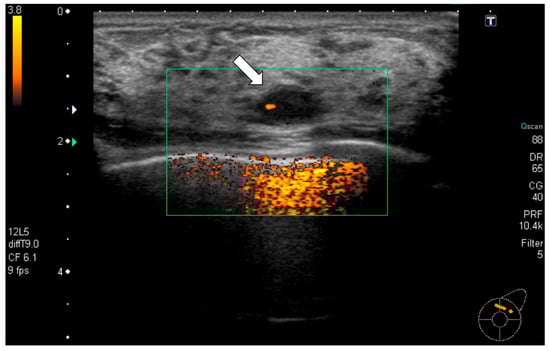

Radiological examination: Screening mammography showed architectural distortion in the central portion of the right breast. Ultrasound revealed a hypoechoic lesion corresponding to this area, diagnosed as a radial scar on core needle biopsy. In the upper outer quadrant of the left breast, an 11 mm oval, well-defined hypoechoic mass with partial blood flow was detected (Figure 1). Core biopsy showed fibrous stroma with capillary proliferation and no malignancy (Figure 2). Follow-up was recommended. However, during the subsequent 11-year interval, no follow-up examinations were performed because the patient discontinued hospital visits for personal reasons. As a result, regular clinical or radiological follow-up could not be conducted during this period.

Figure 1. Ultrasonography (initial): A well-defined oval hypoechoic mass measuring 11 mm (arrow) was observed in the upper outer quadrant of the left breast with partial internal vascularity. Ultrasound-guided core needle biopsy was performed for this mass.